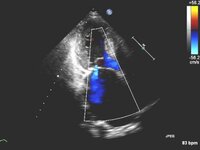

Corte apical de 4 câmaras de folheto mitral posterior instável

Do acervo de Samir Kapadia e Mehdi H. Shishehbor

Corte apical de 4 câmaras de regurgitação mitral 1-2+ posterior